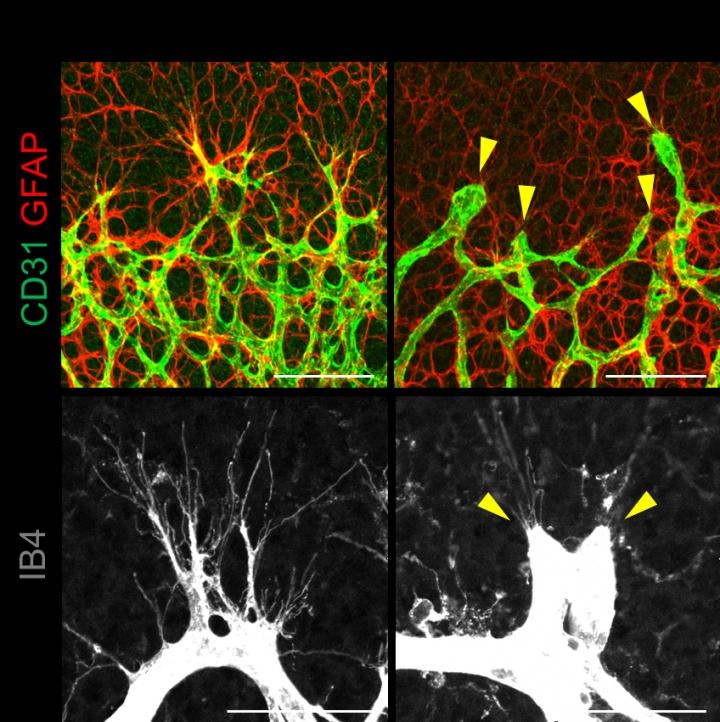

Cells forming the wall of blood vessels, endothelial cells (ECs), are the main actors of angiogenesis. The formation of a new vascular wall is a multistep process that requires coordinated cell migration, proliferation, and junction formation. ECs need to stretch and move and to do that, they use their own "skeleton", the cytoskeleton. The ECs at the front of the migration route are called tip cells and the ones at the base the stalk cells. Tip cells form extensions that help them to creep into the connective tissue. Then, as the new vessel grows out of the existing one, cells also need to create strong bonds to assure a robust wall. Each step is controlled by several proteins whose behavior is only beginning to be understood.

Scientists found that if they overexpress YAP/TAZ, ECs form an excessive number of extensions and boost an abnormal growth of blood vessels, similarly to a tumor. On the other hand, removing YAP/TAZ from 2 day old mice leads to poorly vascularized retina, vision impairment, and internal bleeding in several areas of the brain. In the latter, the ECs' tips are blunt.